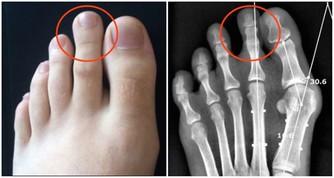

6、傷口難癒合

糖尿病的發生會阻礙血液流通,從而可導致傷口癒合時間延遲,甚至還可損傷神經組織。因為皮膚的傷口癒合需要充分的血液流通,否則會降低治愈能力,如發現有傷口血流不止等異常現象的,建議要及時到醫院接受診斷。